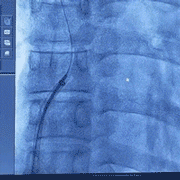

常規(guī)穿刺右股靜脈,送入6F動(dòng)脈鞘管,右心導(dǎo)管、J型鋼絲通過股靜脈,到達(dá)卵圓孔處。導(dǎo)管入上腔靜脈,LAO位下拉入卵圓窩配合導(dǎo)絲向后探查過PFO。

針對(duì)本例極小型卵圓孔未閉(PFO)的介入手術(shù),導(dǎo)絲穿越卵圓孔的過程頗具挑戰(zhàn)性,對(duì)術(shù)者的操作水平提出了較高的要求。

本例手術(shù)中,術(shù)者借助輸送鞘支撐,利用右心導(dǎo)管與導(dǎo)絲協(xié)作探尋卵圓窩邊緣孔隙。經(jīng)過多次細(xì)微調(diào)整與嘗試,對(duì)導(dǎo)管與導(dǎo)絲的角度和力度予以優(yōu)化,最終成功地讓導(dǎo)絲順利通過間隔,并將導(dǎo)管和導(dǎo)絲送達(dá)左上肺靜脈。

嘗試過隔

到達(dá)左上肺靜脈